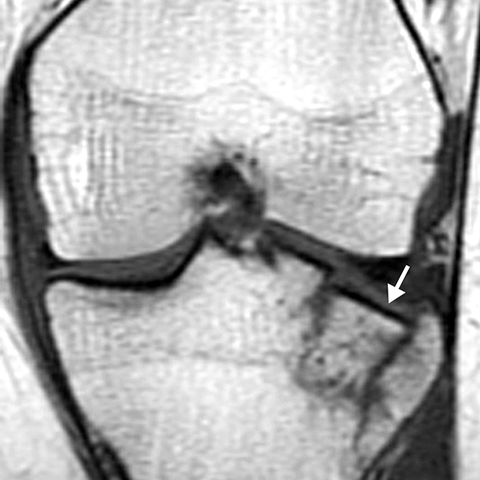

Plateau Fracture [2 of 2]